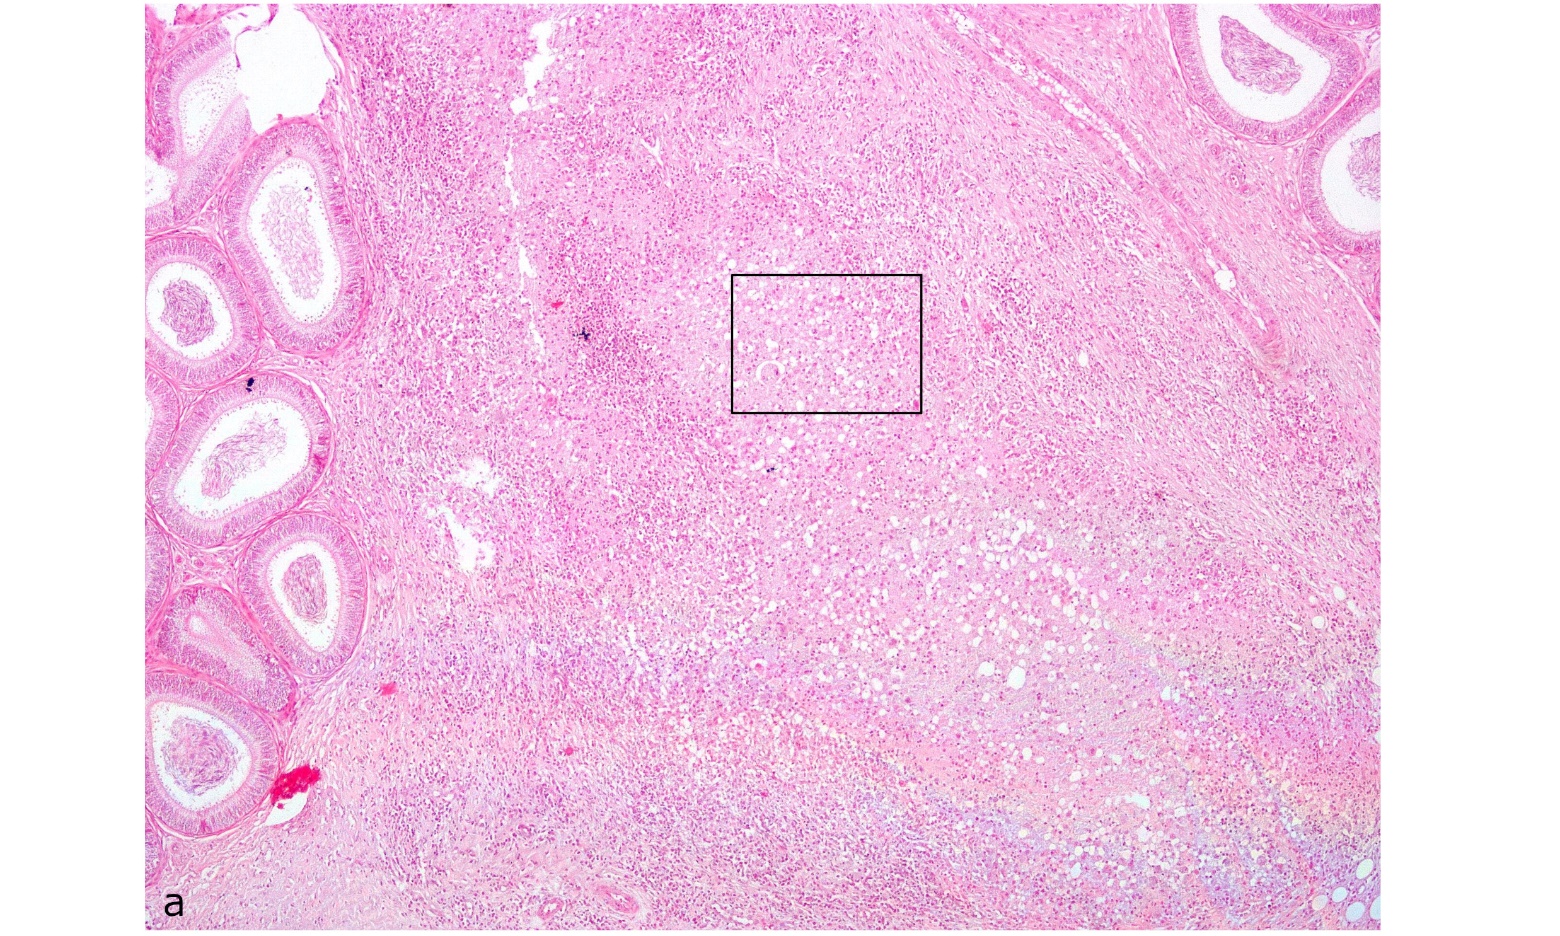

Figure. 2a. Testicle: Interstitial infiltration of eosinophilic material with macrophages, lymphocytes and few neutrophils composing granulomatous orchitis. Hematoxylin/eosin, 40x magnification.

Figure. 2b. Testicle : Detail of boxed area in A showing giant cell (*) and granulomatous inflammatory infiltrate. Hematoxilin/eosin, 200X magnification.

Contrary to the results observed in rabbits (Fort et al. 2012) infected with B. suis biovar 1, the inoculated armadillos did not show macroscopic lesions. In the histopathological studies, lesions were observed only in the epididymis tail of armadillo (B1); this was identical to the lesions observed in domestic species (Foster, 2007). The presence of Brucella in the epididymis and the lesions found in one of the infected animals could be associated with infertility problems in affected armadillos. No histopathological changes were observed in organs from armadillos (A1, B2, B3, and B5) or changes were too minor (e.g., slight infiltration of neutrophils or lymphocytes) to be associated with the infection. However, isolation of B. suis from most organs corroborated the presence of infection in these animals. The discrepancy in the lesions between species could be related to a variation in the pathogenesis of the infection. Future studies are needed to determine the pathology associated with long-term infection of B. suis in armadillos.